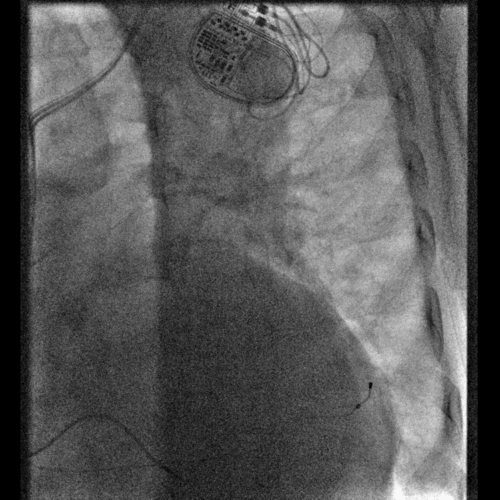

术中冠状窦造影

造影发现在分支静脉处有明显扭曲